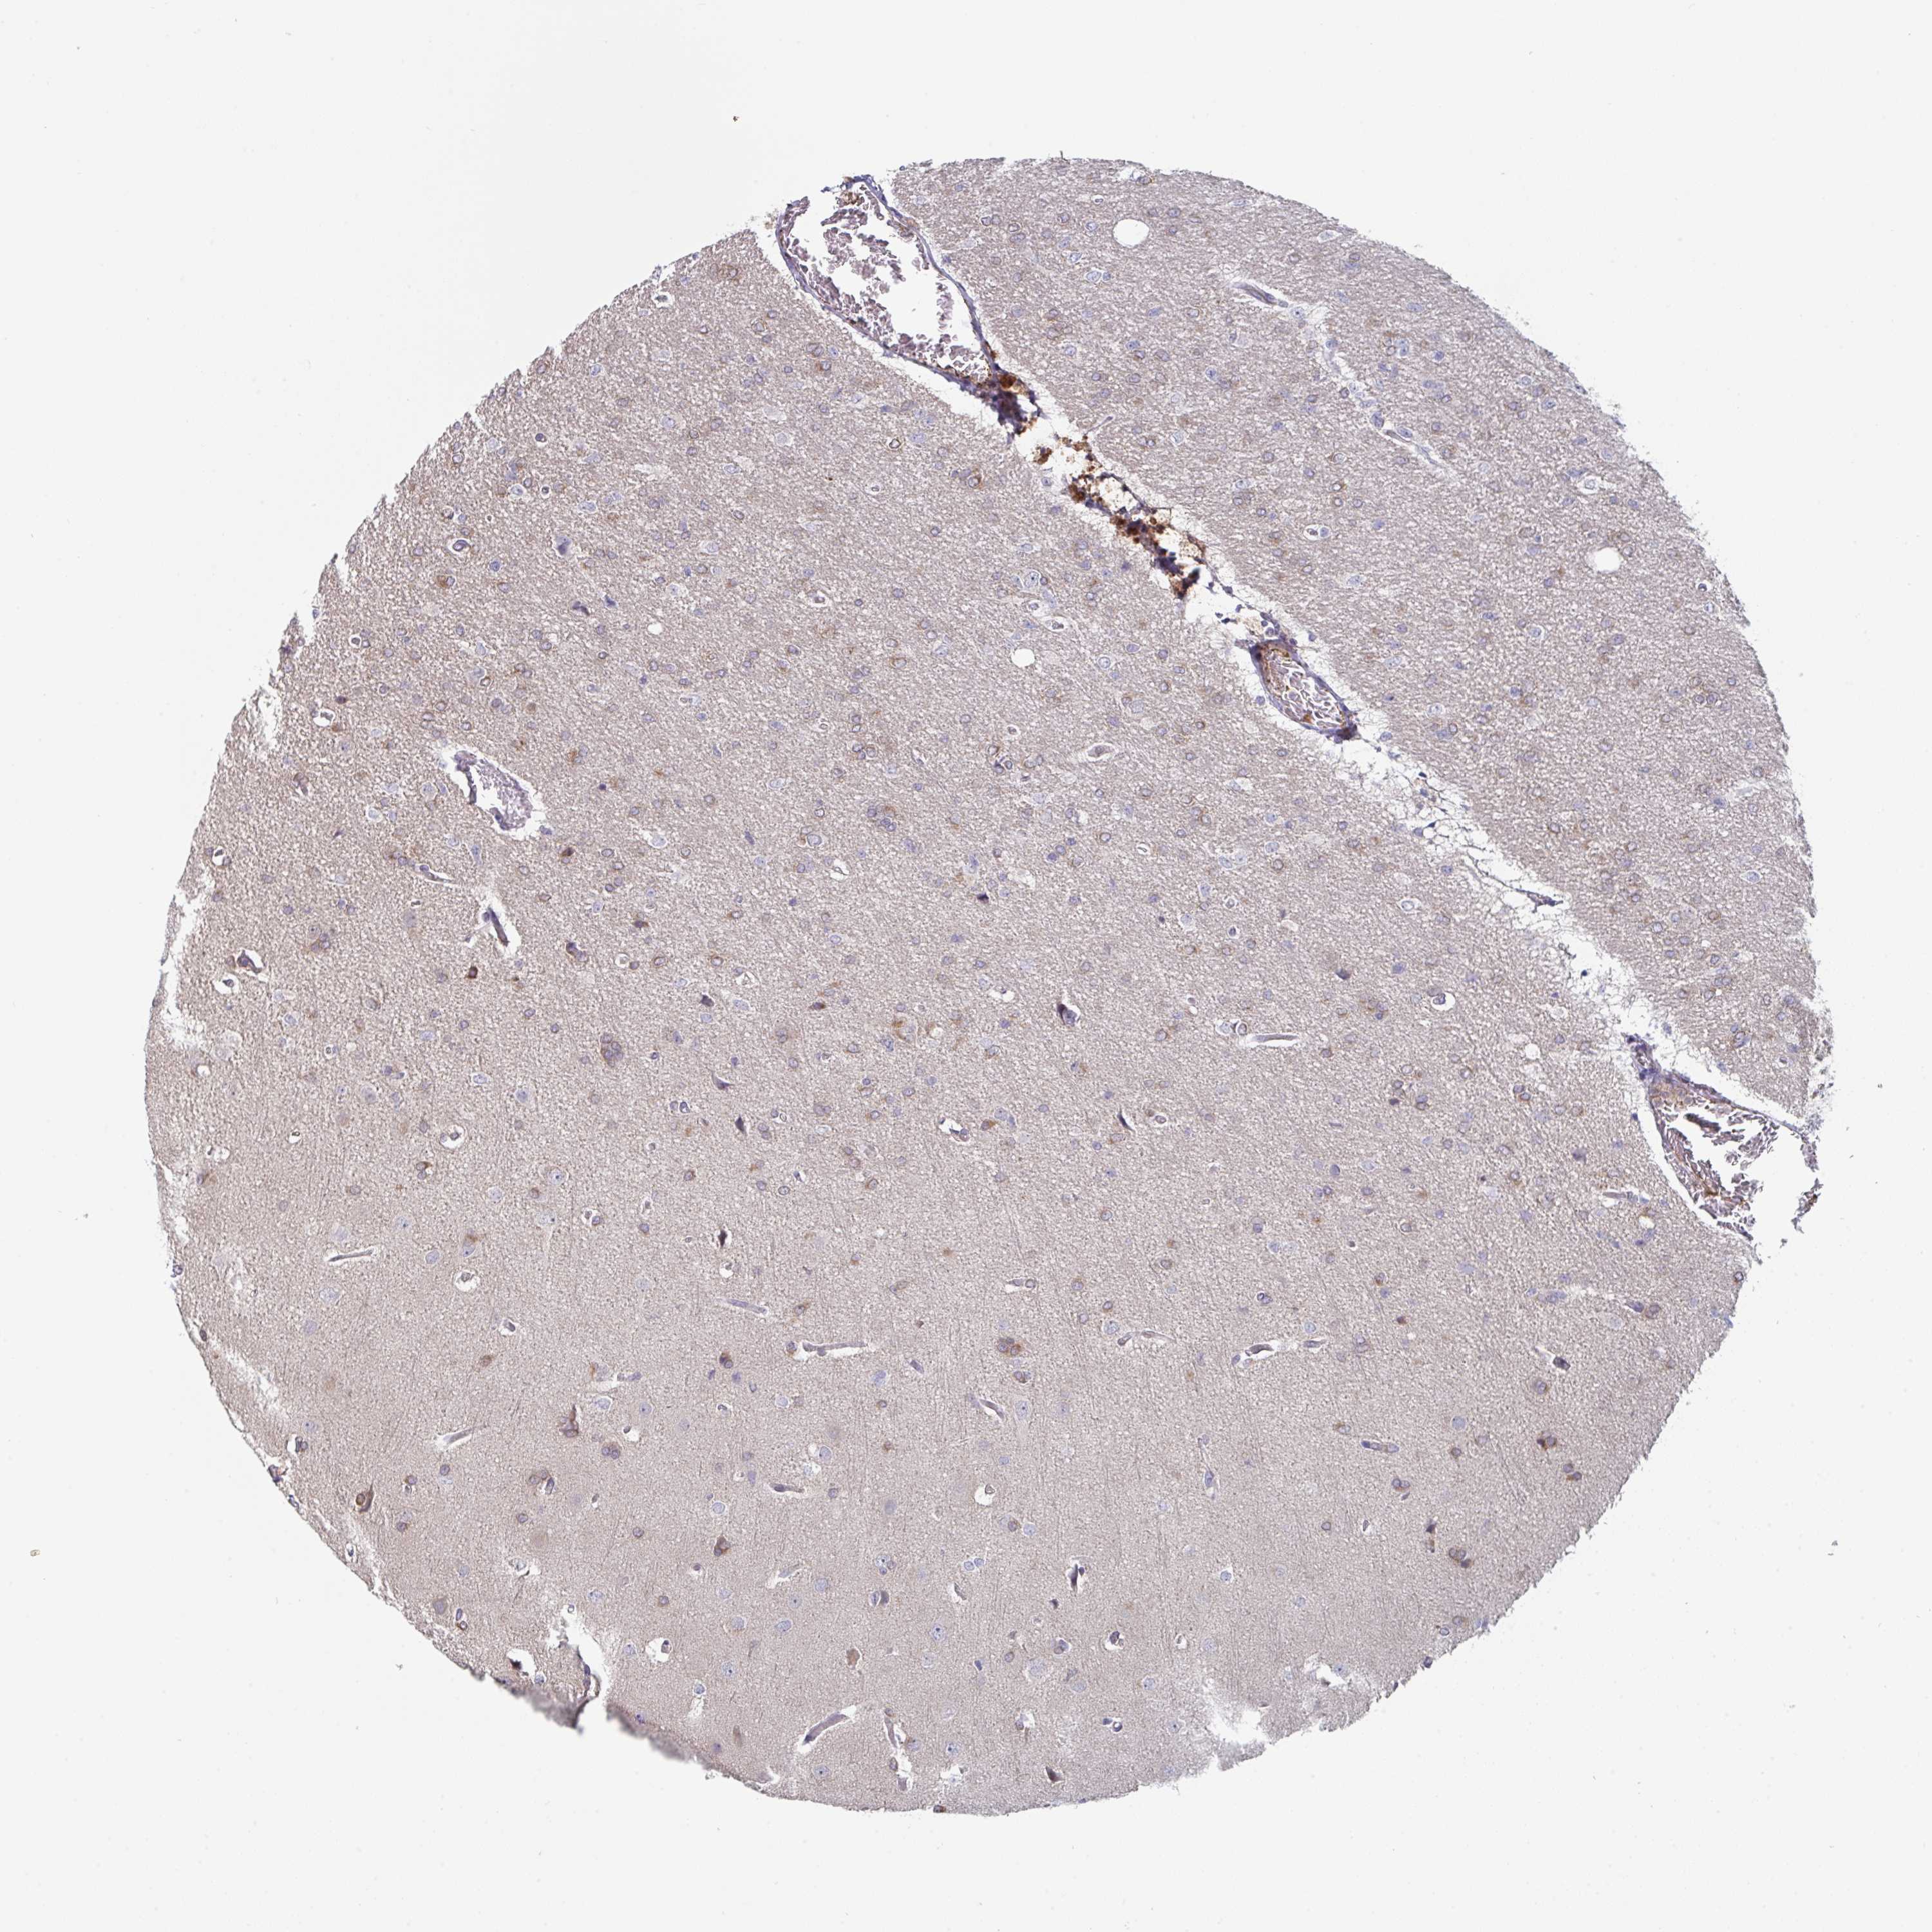

GLIOMA - Protein expressioni

A mouse-over function shows sample information and annotation data. Click on an image to view it in a full screen mode. Samples can be filtered based on level of antibody staining by selecting one or several of the following categories: high, medium, low and not detected. The assay and annotation is described here.

Note that samples used for immunohistochemistry by the Human Protein Atlas do not correspond to samples in the TCGA dataset.

Antibody stainingi

Antibody staining in the annotated cell types in the current human tissue is reported as not detected, low, medium, or high, based on conventional immunohistochemistry profiling in selected tissues. This score is based on the combination of the staining intensity and fraction of stained cells.

Each image is clickable and will lead to virtual microscopy that enables deeper exploration of all samples and also displays staining intensity scores, fraction scores and subcellular localization as well as patient and tissue information for each sample.

Antibody HPA054829

Staining

High

Medium

Low

Not detected

Intensity

Strong

Moderate

Weak

Negative

Quantity

>75%

75%-25%

<25%

None

Location

Nuclear

Cytoplasmic/membranous

Cytoplasmic/membranous,nuclear

Glioma, malignant, Low grade

Glioma, malignant, High grade